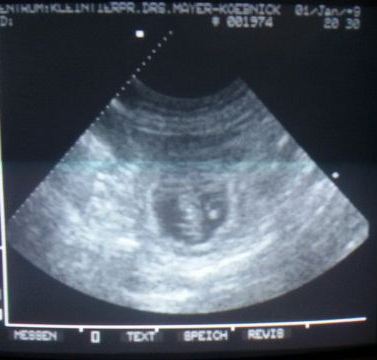

Daka ist tragend!

Die S-Welpis sind also auf dem Weg - wir freuen uns so!

Hier die ersten "Fotos" der Kleinen.